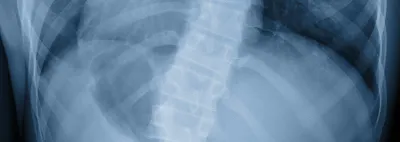

Scoliosis

Scoliosis is an abnormal curvature of the spine, which can lead to uneven posture, back pain, and muscle strain. Typically, it begins as a minor bend in the spine that gradually progresses. In fact, for the diagnosis of scoliosis to be made, there must be a minimum 60-degree sideways curve of the spine. Once the spine has advanced to this stage there are often severe health consequences. The good news is that if the spine is cared for properly during its early stages, it can be prevented from advancing over time.

An x-ray examination is the most effective means of detecting scoliosis. Various orthopedic examinations such as the Adams position test can assist in the diagnosis. Our chiropractors at New Freedom Chiropractic will also examine the hips and shoulders for un-leveling and also check the legs for variation in length which can be a clue to the development of scoliosis.